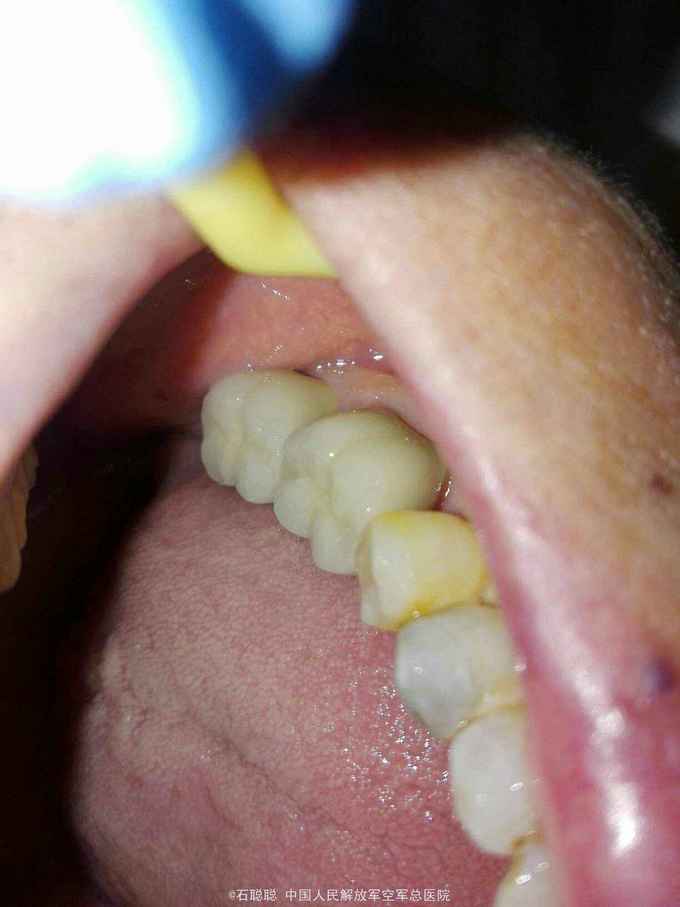

诊断:36、37牙体缺损 治疗计划:36远中、37近中植入纤维桩 烤瓷联冠修复 处置:36、37去除氧化锌暂封,见36远中偏舌侧壁缺损、断面位于龈上1mm,37近中偏舌侧壁缺损、断面平齐龈缘,其余轴壁厚度高度完整 36远中舌侧根管预备桩道,度13mm,1#P钻,37近中舌侧预备桩道,长度14mm,1号P钻,各植入黄玻璃纤维桩一枚,堆树脂核,备牙,取模,比色:A3.5,寄送加工厂,制作临时冠,调合,粘接 一周后复诊: 检查:36、37临时冠完整在位,叩痛-,牙龈未见异常 处置:36、37去除临时冠,清楚粘结剂,试戴36、37银钯合金烤瓷联冠,调合,磨光,粘接

讨论:这个病历中患者68岁,36、37牙槽骨高度有所降低,牙龈随之退缩,导致邻间隙食物嵌塞,龋坏,进一步发展为牙髓炎,牙齿无明显松动,在完善的根管治疗后,制作烤瓷联冠,即可以恢复患牙的咀嚼功能,又能防止食物嵌塞的发生,减缓邻间隙牙槽骨由于食物嵌塞完成进一步的牙龈退缩。